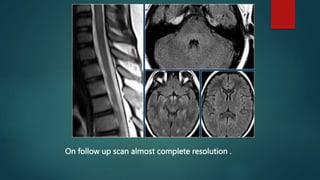

On follow up scan almost complete resolution .